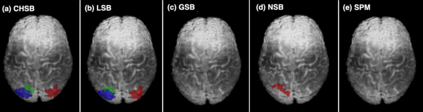

In this paper, we introduce a new Bayesian approach for analyzing task fMRI data that simultaneously detects activation signatures and background connectivity. Our modeling involves a new hybrid tensor spatial-temporal basis strategy that enables scalable computing yet captures nearby and distant intervoxel correlation and long-memory temporal correlation. The spatial basis involves a composite hybrid transform with two levels: the first accounts for within-ROI correlation, and second between-ROI distant correlation. We demonstrate in simulations how our basis space regression modeling strategy increases sensitivity for identifying activation signatures, partly driven by the induced background connectivity that itself can be summarized to reveal biological insights. This strategy leads to computationally scalable fully Bayesian inference at the voxel or ROI level that adjusts for multiple testing. We apply this model to Human Connectome Project data to reveal insights into brain activation patterns and background connectivity related to working memory tasks.